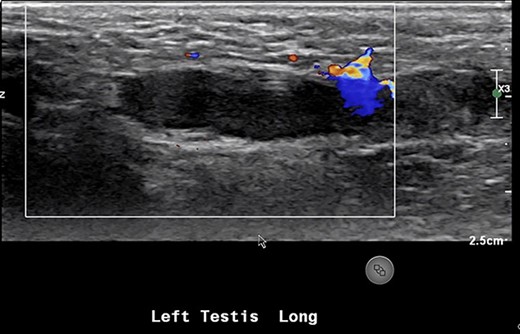

An 18-month-old boy presented to the emergency room with scrotal pain and scrotal discoloration present for 3 hours prior to ED presentation. His parents denied any malodorous or discoloration of his urine. The child was born at term, and immunizations were up to date. On examination, there was no obvious torsion, and testicles were normal lie. He had a scrotal ultrasound showing reduced blood flow in the left testicle, left epididymitis and torsion could not be completely excluded (Fig. 5). He underwent scrotal exploration with findings of normal left testicular lie with no evidence of torsion of the spermatic cord and the epididymis is within normal limits; however, a small hernia containing healthy omentum was identified. The hernia was reduced and repaired with 3-0 vicryl suture.